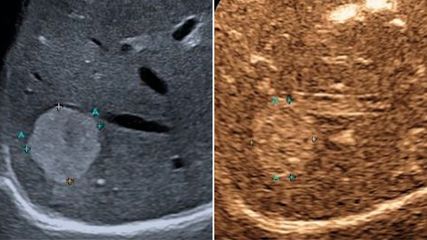

<hr />